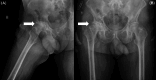

Alkaptonuria is a rare inherited condition caused by elevated levels of homogentisic acid, which confers a characteristic dark color on tissues like cartilage and bones over time, a process known as ochronosis. We present the case of a 62-year-old male patient with a presumed diagnosis of rheumatoid arthritis and severe pain and stiffness in his right hip. Plain radiographs revealed severe right hip osteoarthritis. The patient underwent total hip arthroplasty (THA) without any perioperative complications. The intraoperative findings (black ring-like spot at the femoral head and also at the cartilage and acetabulum) and a more detailed medical history taken postoperatively raised suspicions of alkaptonuria, which was confirmed with the specific exam for alkaptonuria (homogentisic acid levels evaluation in a 24 h urine sample). This report underscores the importance of a thorough medical history and clinical examination of these patients to avoid inaccurate diagnosis and administration of inappropriate therapeutic schemes.